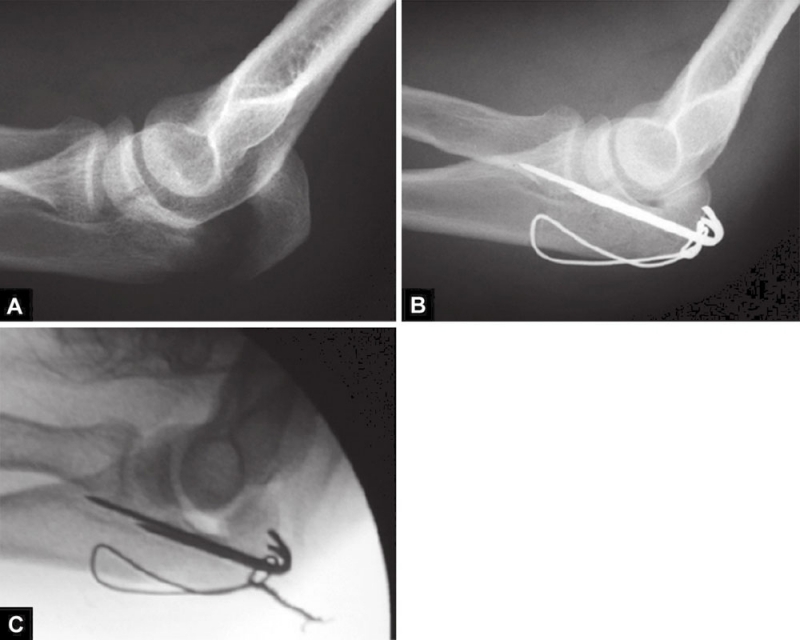

图1A~C(A)关节压缩骨折不易觉察,有经验的医生会注意到从冠状突到鹰嘴尖的关节间隙增宽而得出诊断;(B)如果没有的观察力,医生甚至会在术中X线片检查中都漏诊明显的压缩骨折。医生的注意力完全集中在检查植入物的位置上,因此容易忽略关节不一致;(C)术后摄片显示压缩骨折未复位